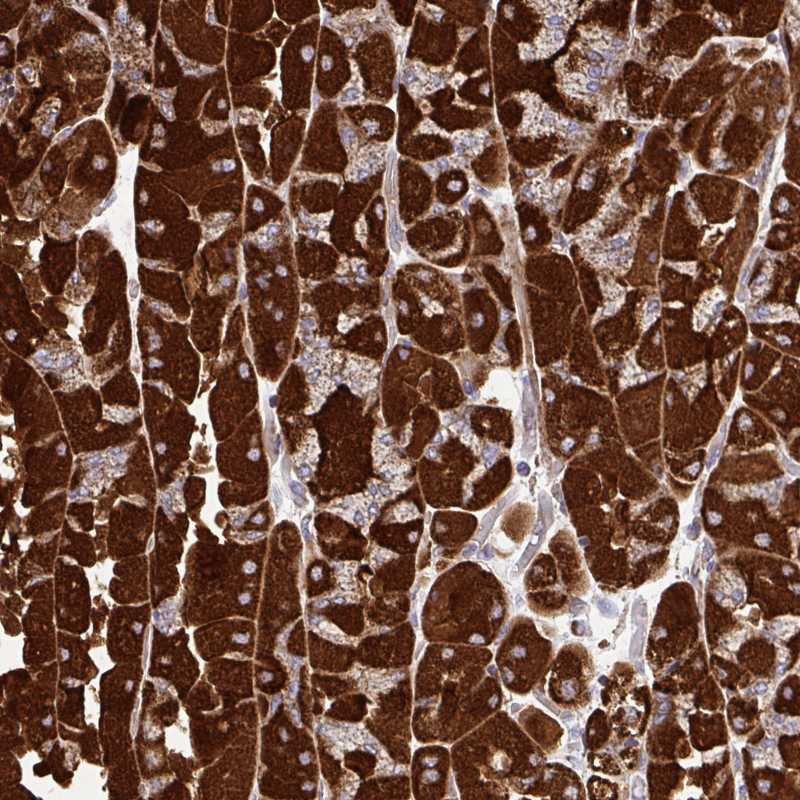

Immunohistochemical staining of human stomach shows strong cytoplasmic positivity in glandular cells.